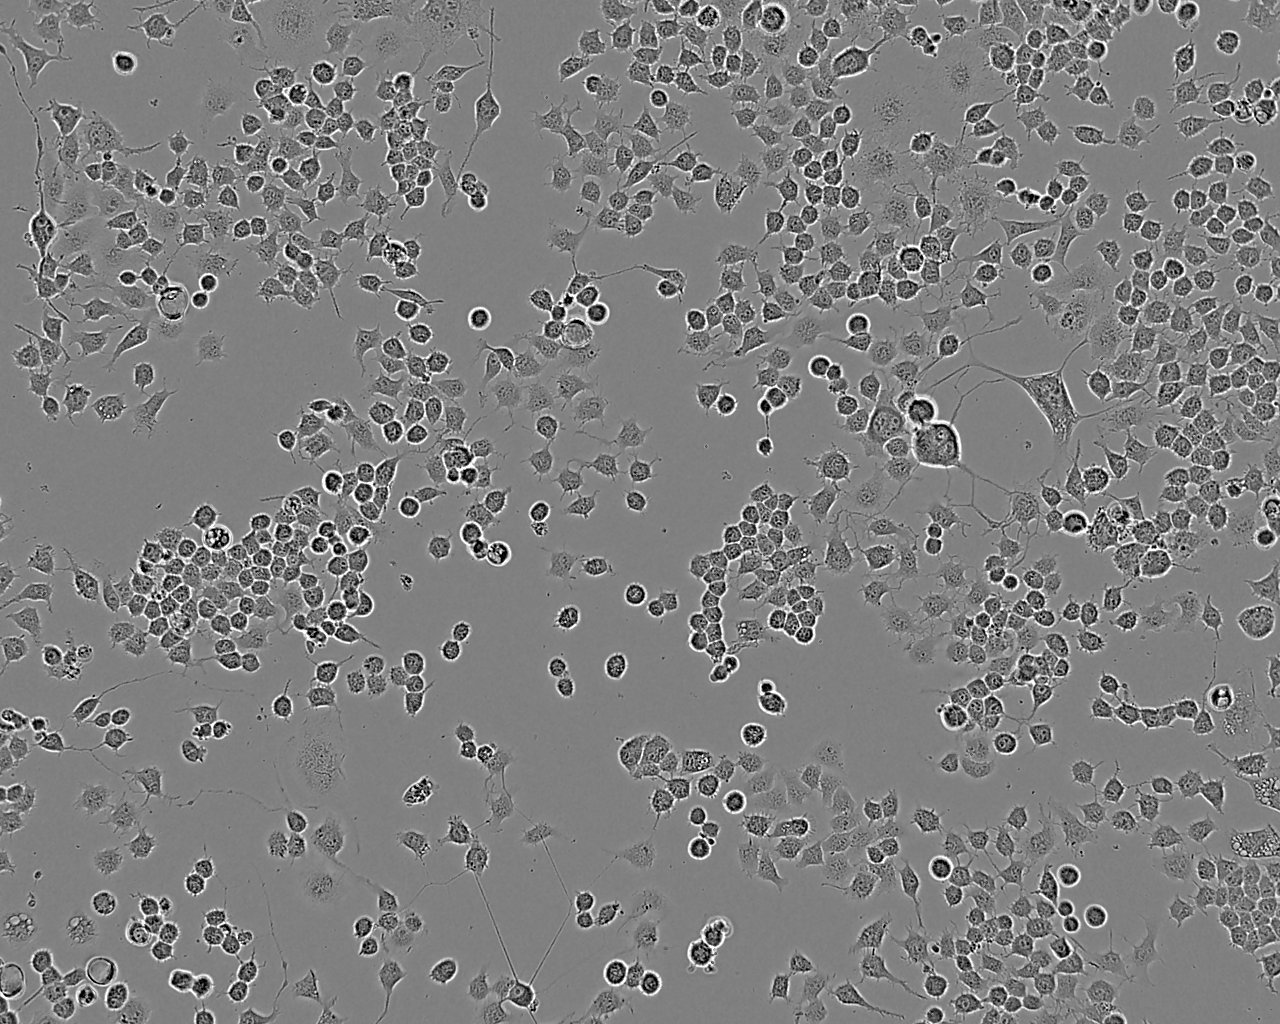

细胞形态:上皮细胞样

细胞生长:贴壁

细胞生长特性:贴壁生长

细胞形态特性:详见细胞说明书